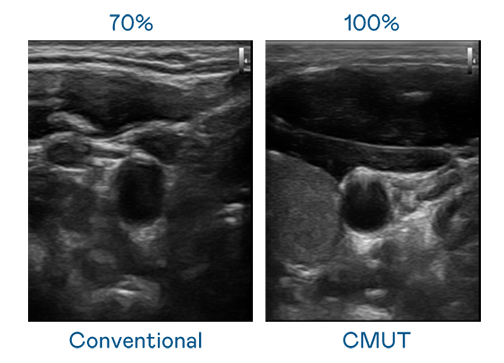

CMUT 技术是一种用电容式微机电元件来产生超音波讯号的技术。与传统 PZT 压电式技术相比,CMUT 频宽增加 30%,更宽频的超音波讯号让影像解析度大幅提升,是实现高影像品质医疗超音波扫描、促进精准医疗发展的关键技术。

超音波影像的解析度高低,首先取决于探头能发出的讯号频宽。开云体育 CMUT 可提供高清晰的超音波讯号,提供高频宽、高灵敏度、影像纹理细节更高的超音波影像,协助医护人员缩短影像判读时间及利用精准的医疗影像进行诊断。